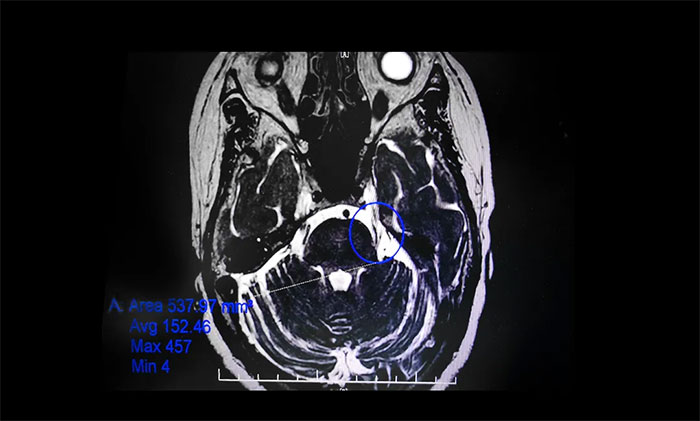

▲ 影像顯示,患者左側(cè)三叉神經(jīng)與周圍小血管關(guān)系密切

在辦理入院手續(xù)后,楊忠旭教授詳細(xì)了解了陳阿姨的病史資料,并為其申請(qǐng)了三叉神經(jīng)MRTA平掃+增強(qiáng)等相關(guān)檢查。結(jié)合影像資料,楊忠旭教授指出患者左側(cè)三叉神經(jīng)與周圍小血管關(guān)系密切,手術(shù)指征明顯,未見(jiàn)明顯手術(shù)禁忌癥。